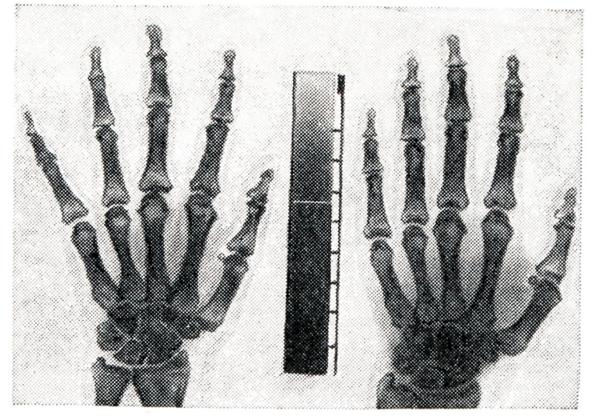

Основной методикой рентгенологического исследования при артрите является рентгенография в двух стандартных проекциях с применением при наличии показаний дополнительных проекций, демонстрирующих более детально локальные изменения суставных поверхностей пораженных суставов (смотри Артрография). С этой же целью, особенно при исследованинии мелких суставов, используют рентгенографию с прямым увеличением изображения(рис. 5).

Хорошие результаты удается получить при электрорентгенографии пораженных суставов, позволяющей наиболее отчетливо выявить мягкие ткани и суставные поверхности (рис. 6).

При этом существенную помощь оказывает рентгеноденситометрия, проведение которой весьма целесообразно при сравнительном динамическом изучении одноименных суставов, особенно при одностороннем поражении. Рентгеноденситометрия может быть использована не только для целей диагностики, но и для контроля эффективности проводимого лечения, поскольку она точно отражает как процессы деминерализации кости при активно протекающих артритов (рис. 7), так и репаративные процессы при обратном развитии воспалительных изменений.

Рентгенологическая симптоматика артрита многообразна и включает следующие признаки: остеопороз во всех его разновидностях; иногда расширение суставной щели или чаще ее сужение (тотальное или частичное) в связи с наличием деструктивных изменений в костно-хрящевых элементах сустава; краевые костные дефекты, так наз. узуры, на суставных поверхностях как следствие деструктивных процессов; наличие очагов деструкции в околосуставных участках костей; образование секвестров, нередко наблюдаемое при специфических, в частности туберкулезных, артритов (рис. 8); периостальные наложения в области метафизов длинных трубчатых костей, а также реактивный остеосклероз; изменения рельефа суставных поверхностей костей и краевые костные разрастания на костях, образующих сустав; вывихи и подвывихи, возникающие в результате деформации суставов при некоторых формах артрита (рис. 9).